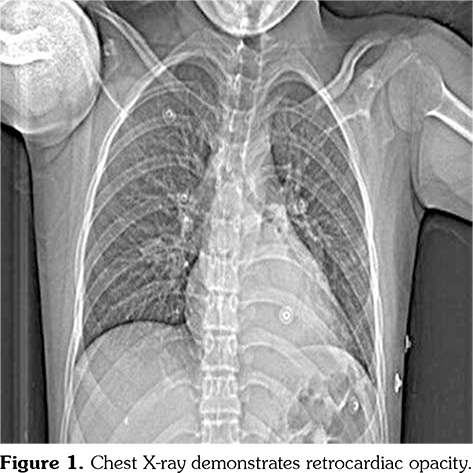

Chest X-ray showed retrocardiac hyperdensity on admission (Figure 1). Diagnostic investigations for tuberculosis were all negative. On bronchoscopy; left lower lobe bronchus was narrowed due to the external compression and abundant viscous secretions were observed. Computed tomography (CT) angiography was performed, which was consistent with multiple PAAs bilaterally (Figure 2). Diagnostic investigations such as echocardiogram and lower extremity venous Doppler ultrasonography, renal function evaluation, eye examination, abdominal ultrasound, and rheumatologic tests revealed no pathological findings. Our patient’s investigational tests for PAA were negative for cardiovascular disease, pulmonary hypertension or any infection.

Pathergy test was performed due to the presence of recurrent oral and genital ulcers, supporting the diagnosis of BD. Pathergy test was positive and he was diagnosed as BD according to the history, physical examination and laboratory findings. Monthly intravenous cyclophosphamide pulses combined with high dose methyl-prednisone were initiated and followed by prednisolone 2 mg/kg/day. Afterwards, left lower lobectomy was performed. Pathological examination revealed PAA with thrombus in the lumen, fibrosis and lymphoplasmacytic inflammatory cell infiltration adjacent to small- and medium- sized vessels (Figure 3). He was clinically well after lobectomy and admitted for the second pulse immunosuppressive therapy. Meanwhile, CT angiography was performed to evaluate the aneurysm at the right lower lobe which showed regression of PAA from 16 mm to 6 mm in diameter. Endovascular embolization was planned for the right lower lobe PAA. However, unfortunately, he presented with massive hemoptysis five days later. The patient passed away with massive hemoptysis originating from the right lower lobe PAA.